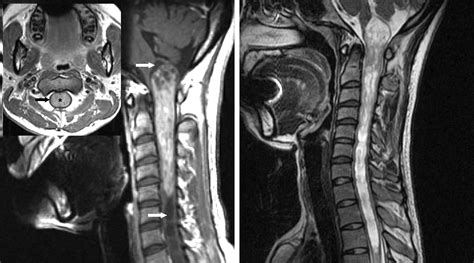

A spinal cord neoplasm is an abnormal growth of cells within or adjacent to the spinal cord. These growths can be classified based on their location: intramedullary (inside the spinal cord substance), extramedullary-intradural (inside the covering of the spinal cord but outside the cord itself), or extradural (outside the spinal cord covering, usually involving the vertebrae). Regardless of the location, these masses exert pressure on the delicate nerve fibers, leading to the clinical manifestations patients experience.

Cervical (Neck) Pain, weakness in both arms and legs, sensory loss in limbs.

Once a physician suspects a spinal cord neoplasm based on the described symptoms, they will utilize advanced imaging to confirm the diagnosis. The goal is to identify the size, exact location, and potential nature of the growth. Magnetic Resonance Imaging (MRI) is the gold standard for evaluating spinal cord tumors because it provides high-resolution images of the spinal cord, nerve roots, and surrounding tissues.

In some cases, your medical team may suggest a contrast-enhanced MRI to better visualize how the tumor interacts with the spinal cord tissues. Additionally, if the symptoms are ambiguous, doctors might conduct an electromyography (EMG) or nerve conduction study to rule out other peripheral nerve conditions that mimic Spinal Cord Neoplasm Symptoms.